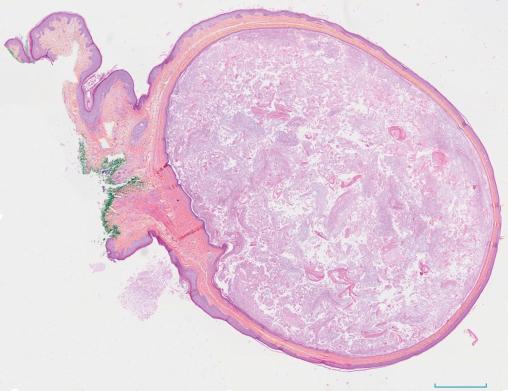

Le traitement repose sur l’exérèse monobloc, qui permet aussi l’analyse histologique (fig. 2).

Le kyste épidermique, ou « épithélial » ou « infundibulaire », est une pseudotumeur annexielle bénigne. Il s’agit de la cause la plus fréquente de kystes cutanés. Il dérive de l’épithélium infundibulaire d’un follicule pileux avec, en son sein, des lamelles de kératine et du sébum, circonscrits par un épithélium malpighien. Il siège le plus souvent au niveau du cuir chevelu (classique « loupe »), du visage, du cou, du dos et du scrotum.

Sur le plan clinique, il est habituellement asymptomatique. Il prend la forme d’une lésion kystique, sous-cutanée ou intradermique, ronde, de 5 à 50 mm de diamètre, à surface lisse, rénitente et de consistance pâteuse à la palpation, parfois centrée par un orifice de petite taille. Il contient une substance grasse, compacte, de couleur blanc jaunâtre, à l’odeur fétide caractéristique.